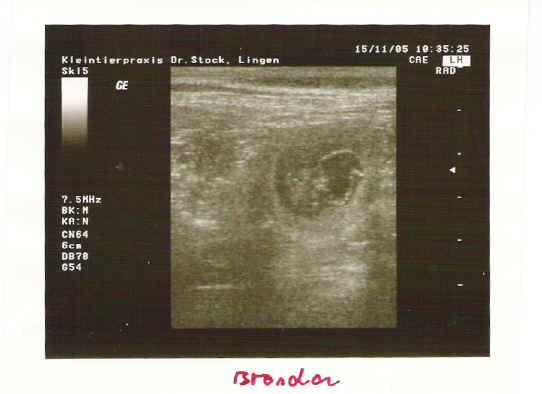

Neue US - Aufnahmen vom 31. Tag der Tragzeit von Brenda v. Weinbacher Land.

Eine Hündin trägt ca.63 Tage, mal mehr, mal weniger. Unsere Hündin hat sich den 64. Tag ausgesucht. Nach 5 -6 Wochen kann man der Hündin sehr gut ansehen, dass Sie tragend ist, denn der Bauchumfang hat stark zugenommen und das Gesäuge ist stark abgeschwollen. Hier sieht man eine Hündin mit einer Tragzeit von 50 Tagen. Vom rechten Horn ist nur der zum Geburtsweg führende Teil dargestellt.